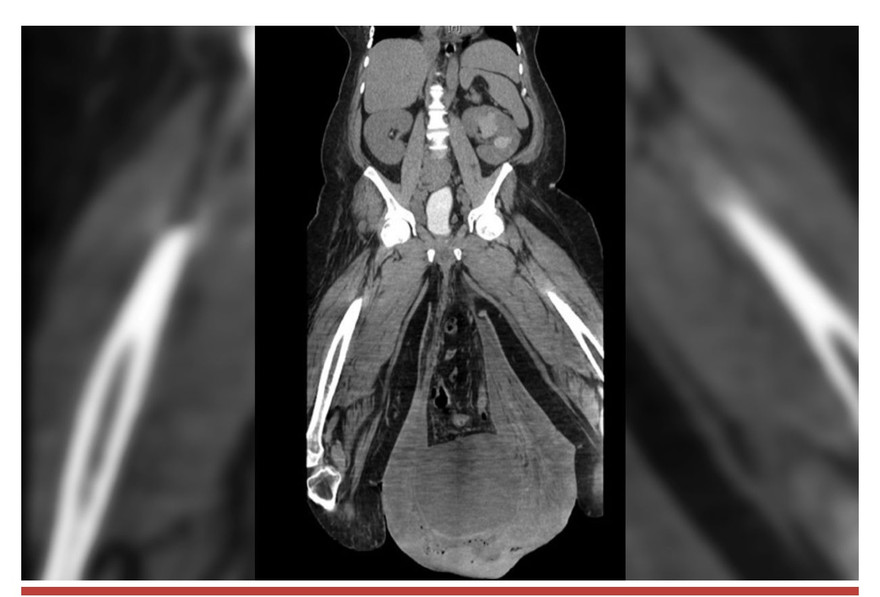

Hình ảnh chụp cắt lớp tinh hoàn của người đàn ông Panams

Kết quả chụp CT cho thấy thoát vị ở háng, một túi khí 12,8 cm dưới da và một bể chứa nước tiểu đã khiến thận của anh ta phồng lên.